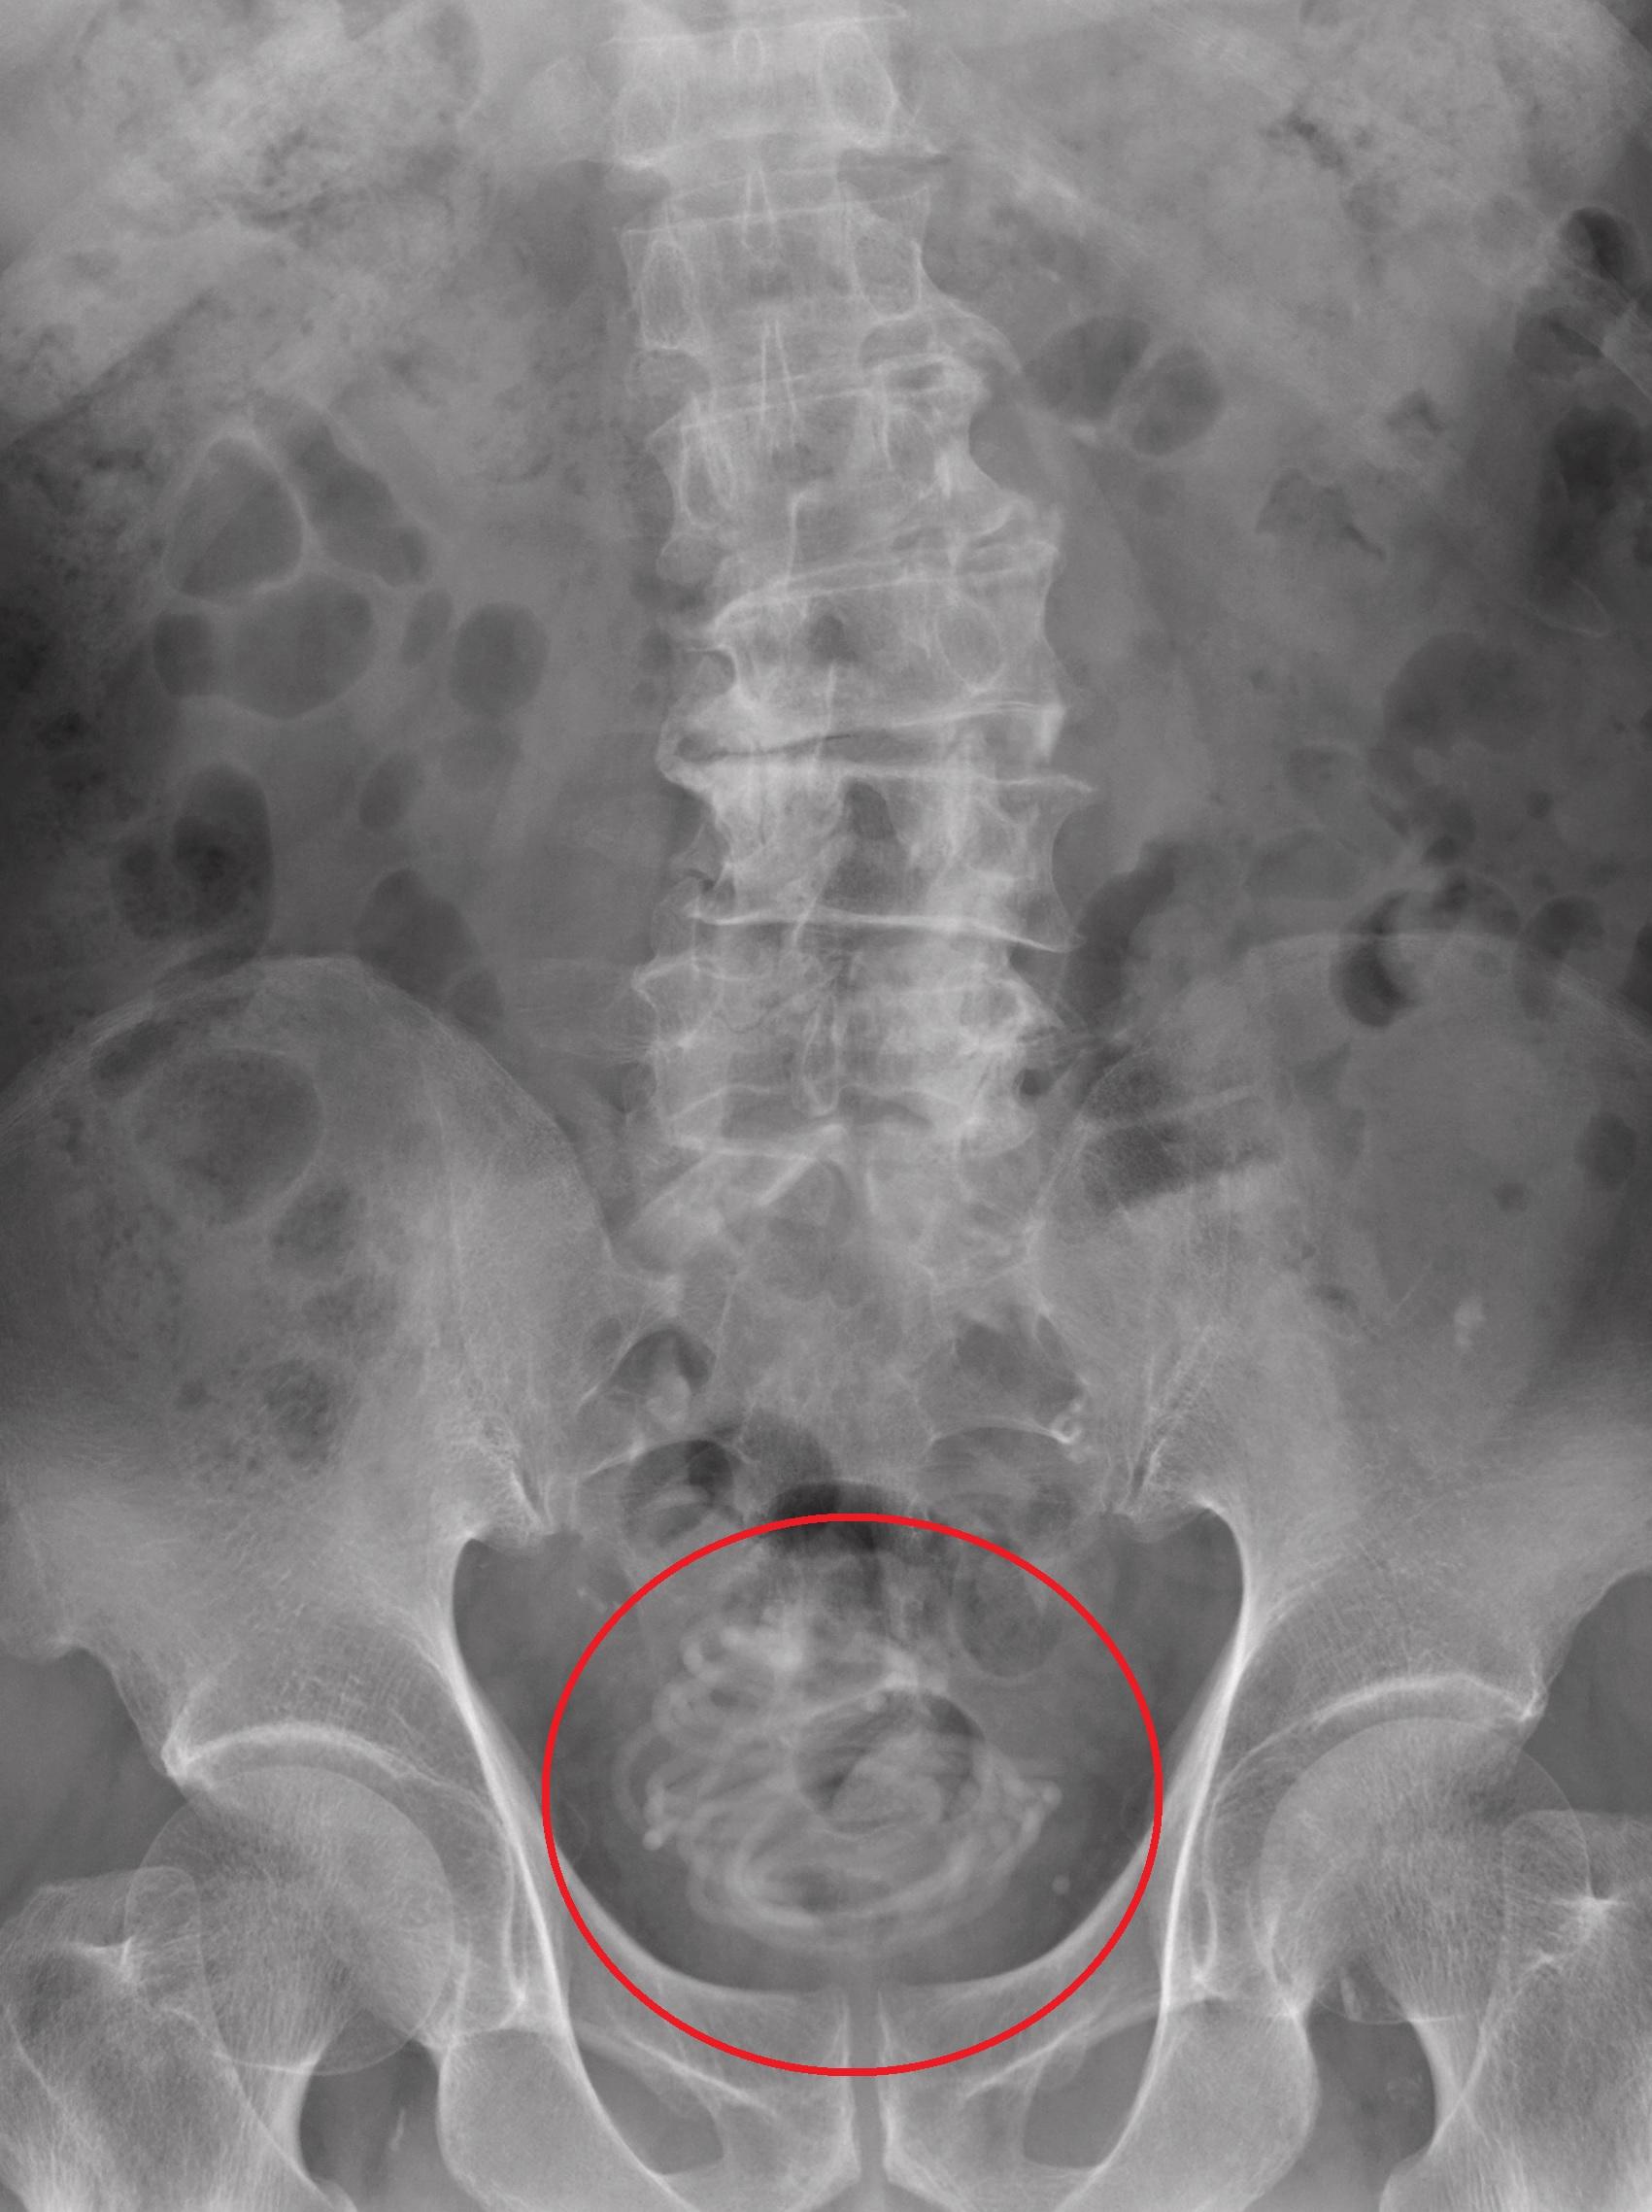

膠跳繩從尿道插進膀胱裡。(互聯網)

匪夷所思……日本櫪木縣一名79歲老翁因排尿困難、小便時有灼熱感且常覺疼痛,到當地一間大學醫院求醫,醫生替他做X光檢查,赫然發現他膀胱裡竟有一條長長的纏繞物。

該條跳繩長約2.3米,在老翁膀胱裡已打結纏繞成球狀,醫生無法沿原先進入的路徑取出,最後只好做內窺鏡微創手術,在老翁腹部割開一個小切口將跳繩取出。老翁於手術後並無大礙,也沒出現併發症。